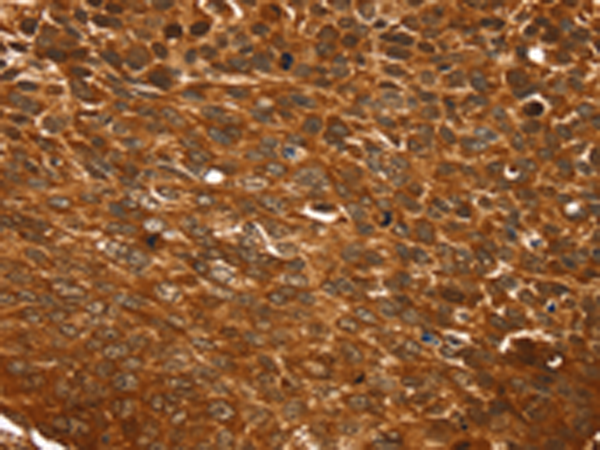

IHC positive control: |

Human esophagus cancer and Human lung cancer |